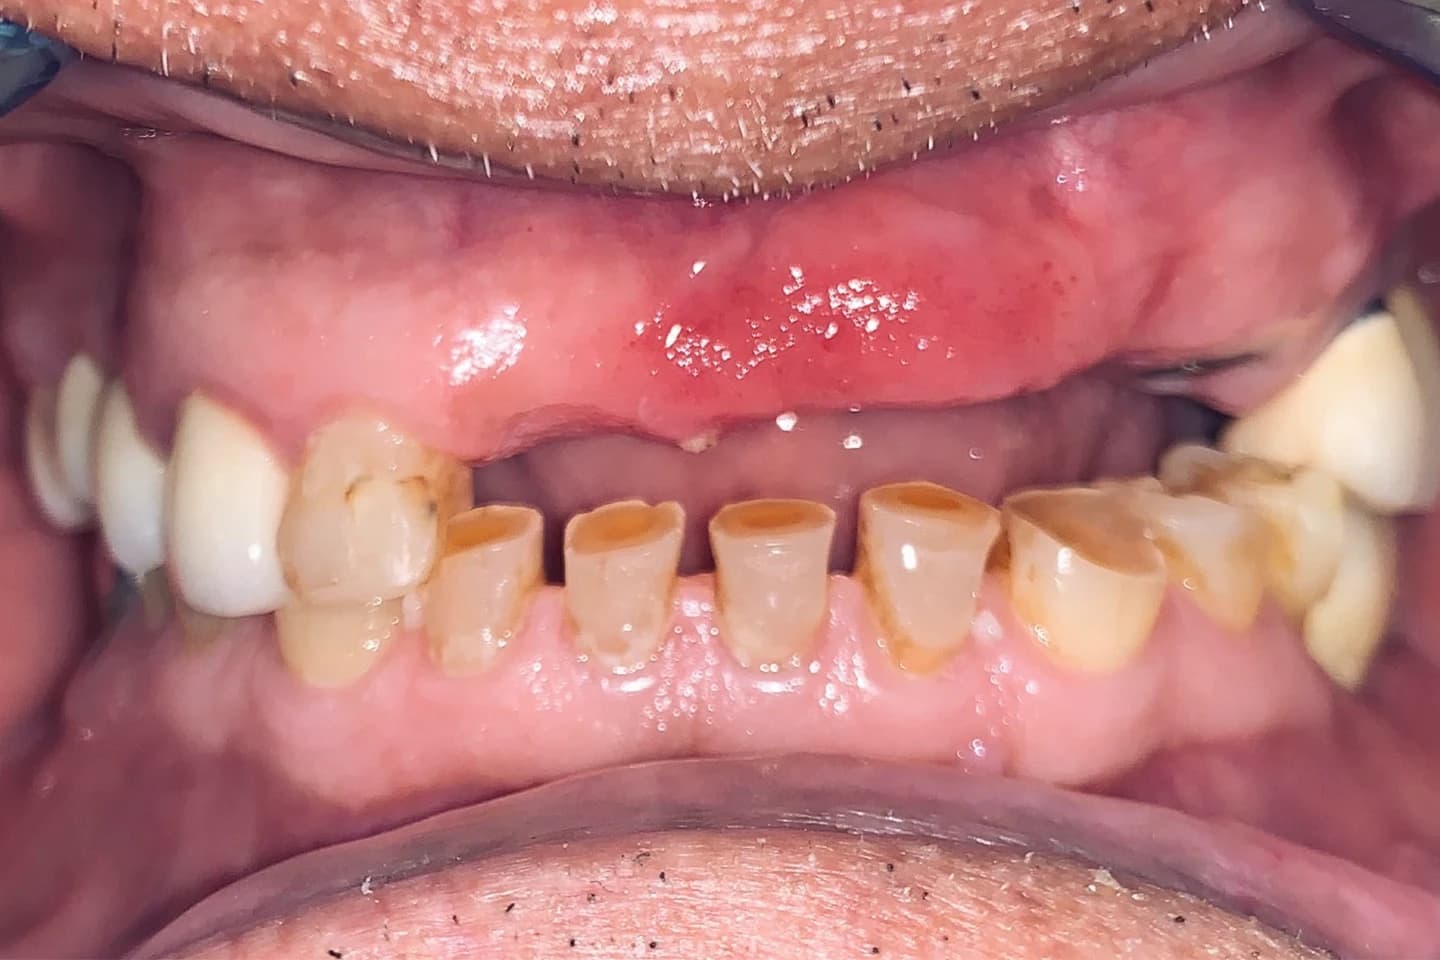

Zubi pre i posle

Osmeh i oblik zuba slike - pre i posle

Stomatološka ordinacija Marco Dental Tourism svakodnevno stvara neverovatne transformacije osmeha. Pogledajte galeriju naših radova i uverite se u moć stomatologije!

Krunice za zube - pre i posle

- Pogledajte kako krunice mogu da zaštite i obnove oštećenost kada su u pitanju zubi, vraćajući im estetiku i funkciju. Galerija radova će vas inspirisati da i vi transformišete svoj osmeh.